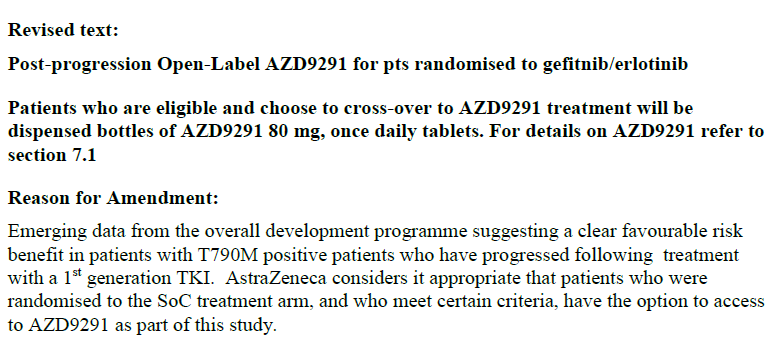

йӮЈд№Ҳдёәд»Җд№ҲиҰҒжңүcrossoverзҡ„и®ҫи®Ўе‘ў��пјҹзқҖе®һеңЁFLAURAеҗҜеҠЁеҲқжңҹ����пјҢжҳҜдёҚе…Ғи®ёcrossoverзҡ„����пјҢдҪҶйҡҸзқҖAURAзі»еҲ—з ”з©¶зҡ„дёҖзӣҙд№җжҲҗ����пјҢеҘҘеёҢжӣҝе°је·Із»ҸжҲҗдёәT790MзӘҒеҸҳжӮЈиҖ…зҡ„ж ҮеҮҶдәҢзәҝжІ»з–—и®ЎеҲ’����пјҢжӯӨж—¶еҶҚжҰЁеҸ–crossoverжҳҫ然жңүжӮ–дәҺдјҰзҗҶ����пјҢеҗҢж—¶д№ҹдјҡеўһж·»е…Ҙз»„зҡ„йҡҫеәҰ����пјҢеӣ жӯӨеңЁ2015е№ҙ4жңҲ13ж—Ҙ����пјҢFLAURAдҝ®ж”№з ”究计еҲ’并е…Ғи®ёжҜ”з…§з»„еҲҮеҗҲжқЎд»¶зҡ„жӮЈиҖ…дёҫиЎҢcrossoverпјҲеӣҫ7пјү��гҖӮ